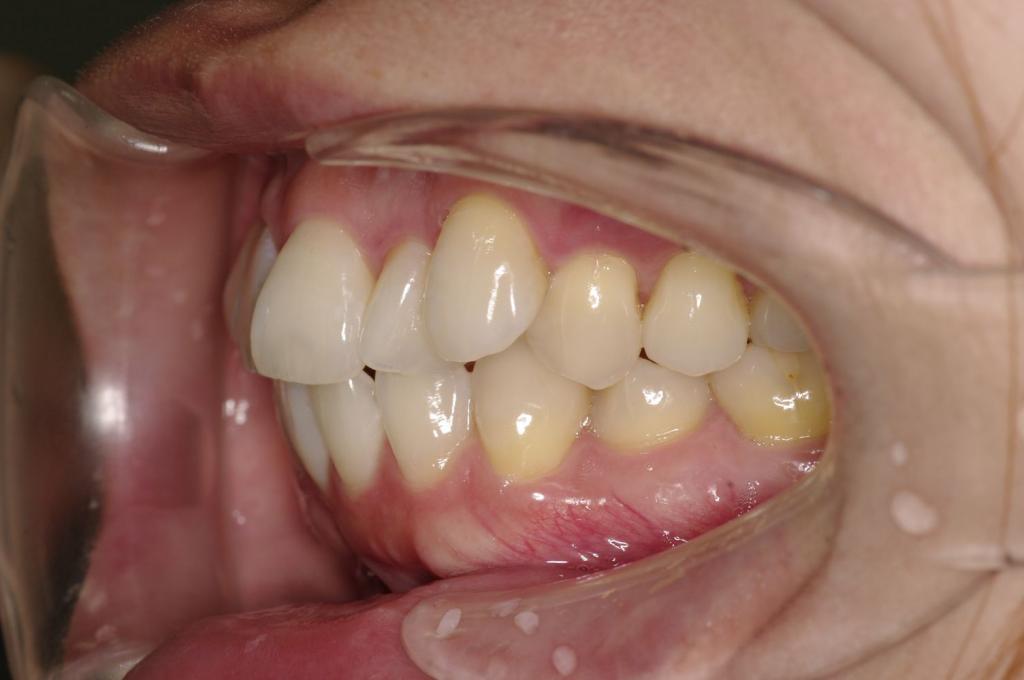

前歯、出っ歯・開咬の矯正治療

(治療期間、治療前後写真、治療方法、費用)WORKS